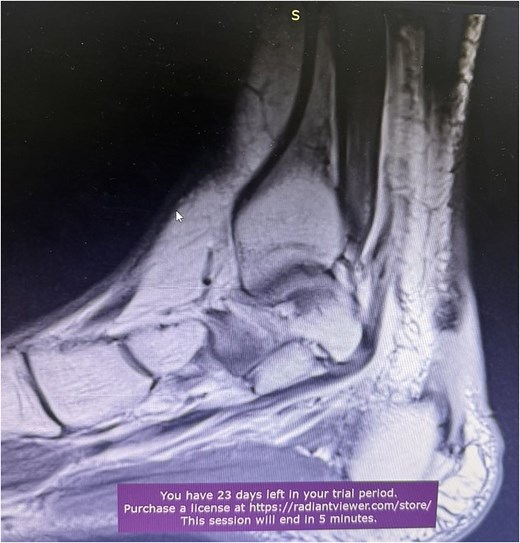

A comprehensive physical examination provided significant insights into the patient’s condition following the Achilles tendon rupture. The Thompson test was particularly noteworthy, showing an absence of plantar flexion upon calf compression, strongly indicating a complete tendon rupture. The examination further revealed a palpable gap in the Achilles tendon and increased passive dorsiflexion. Symptoms included significant weakness, difficulty walking and heel pain. Imaging studies, including X-rays (Fig. 2) and magnetic resonance imaging (MRI) (Fig. 3), confirmed these findings, showing an acute rupture with retracted tendon edges, distinguishing it from chronic condition and suggesting a possible link to the vigorous ultrasound therapy [3].